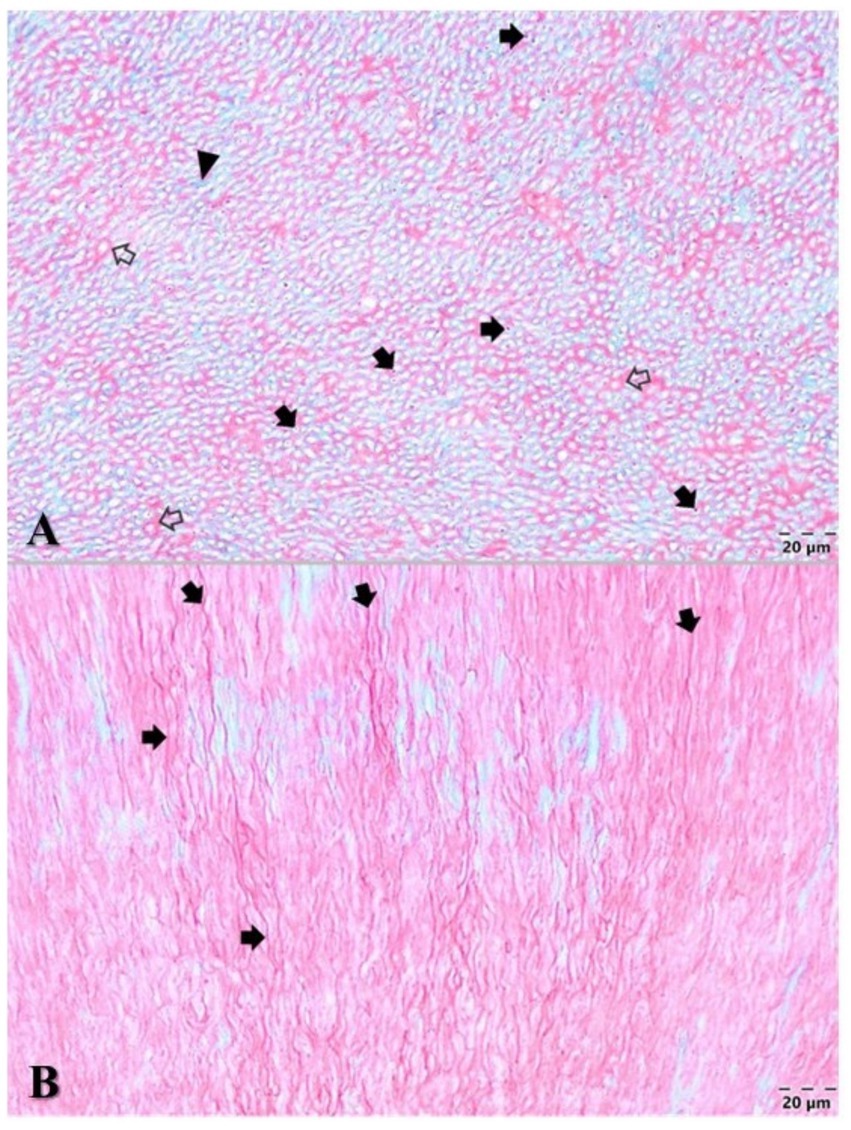

Wild animals in captivity are prone to developing dental diseases. Pink discoloured canine teeth in jaguars are often seen in wildlife photographs but are rarely reported in the literature, and none have been formally investigated. Within 24 hours post-mortem, the oral cavity of a zoo jaguar was investigated using computed tomography (CT). One pink discoloured canine tooth was atraumatically extracted, fixed and stained for histological and transmission electron microscopic (TEM) examination. The intravitam pink discoloured canine tooth had no periodontal or periapical lesions, and microscopically the dental pulp presented numerous ectatic blood vessels with numerous thrombi that occluded the blood vessels. A high percentage of thrombi presented the retunneling phenomenon. Fluorescence imaging confirmed the presence of haemoglobin in the dentinal tubules. The study, the first of its type, sheds light on an intravitam pink discoloured canine tooth opening, a hitherto unexplored topic in zoo dentistry. For the skull to be accepted into the zoological collection of the National Institute of Biology, the extracted canine tooth had to be replaced by a 1:1 scale prosthodontic reconstruction, macroscopically identical to the natural tooth. Prosthodontic reconstruction was performed using computer-aided design and manufacturing (CAD/CAM) technology. The study, the first of its type, investigates an intravitam pink discoloured canine tooth in a jaguar, a hitherto unexplored topic in zoo dentistry, and describes its prosthodontic reconstruction.